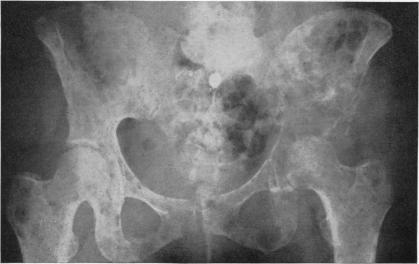

Adrenalectomy for mammary cancer; surgical technic of bilateral one-stage adrenalectomy in man.

Ann Surg. 1952 Oct;136(4):595-603.